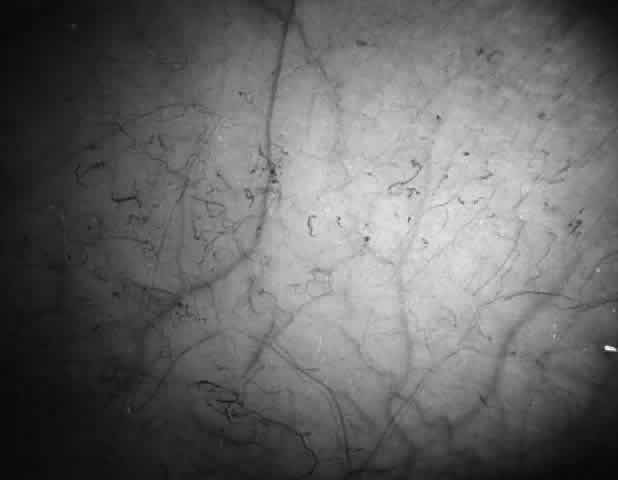

Conjunctival Sickle Sign

Abnormalities of the bulbar conjunctival blood vessels provide direct evidence of the vaso-occlusive process and were one of the earliest reported ocular changes.38–43 These abnormalities are believed to be the result of flow obstruction or impedance by sickled cells. The severity of the conjunctival changes ranges from linear dilatations to isolated groups of truncated, comma-shaped segments. These changes have been correlated with the ISC count, Hb S concentration, and the intraerythrocytic hemoglobin concentration (Fig. 1).44–47 Although they are known as the conjunctival sickle sign, these vascular abnormalities are not completely pathognomonic of sickle cell disease: in rare cases they are seen in patients with AIDS, chronic myelogenous leukemia, and other vaso-occlusive diseases.47–49